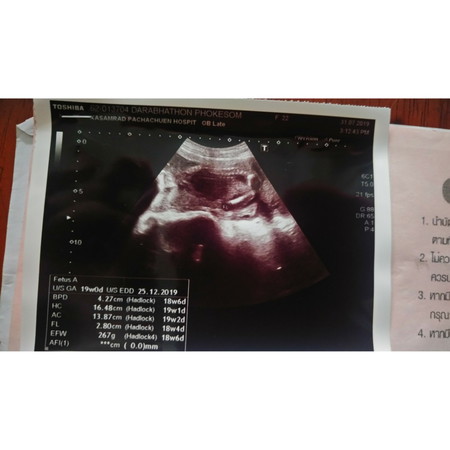

แม่ๆบ้านไหนมีประสบการณ์ดูแผ่นฟิล์มช่วยพ่อแม่บ้านนี้หน่อยจ้า แม่ดูไม่ออกว่าคืออะไร

FL : ความยาวกระดูกต้นขา BPD : ความกว้างศีรษะ HC : เส้นรอบวงของศรีษะ AC : เส้นรอบวงของท้อง EFW : ค่าประมาณน้ำหนักตัวของทารกในครรภ์ AFl : ค่าปริมาณน้ำคร่ำ รวมจากการวัด 4 ตำแหน่ง ประมาณนี้ค่ะคุณแม่😊✨

ในรูปคือยังไม่เห็นเพศน้องหรอค่ะ